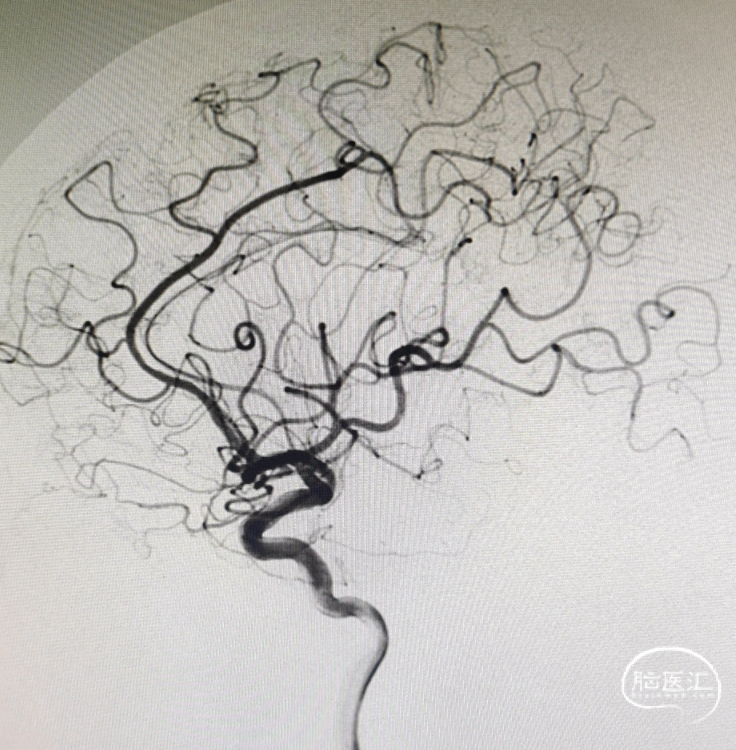

术后影像

动脉瘤致密栓塞,瘤腔内血栓形成;各分支血管显影正常。